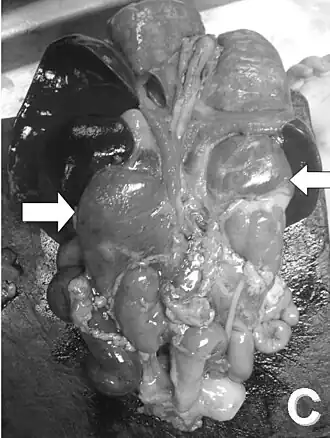

| Exame de um bebê após sua morte. As setas indicam as supra-renais hiperplásicas. | |